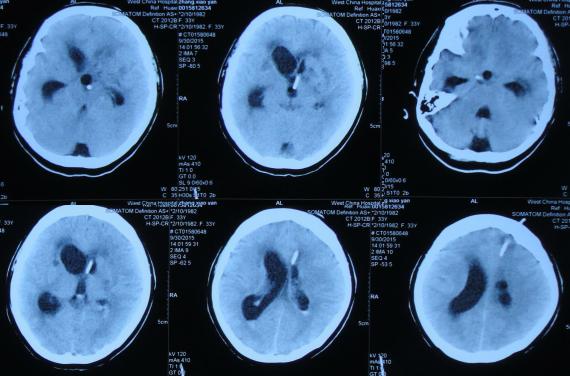

2016年6月3日住入李小勇脑脊液中心,入院时:卧床,反应慢,表情淡漠,言语迟钝(问答无反应),吞咽困难,只能鼻饲流食,头部有多处手术疤痕,右下肢自主活动差,但刺激后能动(图-25);入院第2天即2016年6月5日,头部CT示脑积水,脑室粘连,脑萎缩(图-26)。

图-26:2016年6月5日头部CT入院时

入院后4天即2016年6月7日,进行了脑室腹腔分流管取出术+脑室腹腔分流泵取出术+脑室外引流术+脑室腹壁外引流术+透明隔造瘘术,术后当天查头部CT示脑室引流术后(图-27)。

图-27:2016年6月7日术后头部CT

入院治疗2个月时间内,虽脑室缩小,但仍有结核性脑脓肿(图-28、图-29),且病情持续加重致昏睡,不能遵嘱活动,不能言语。

图-28:2016年6月12日

图-29:2016年6月22日